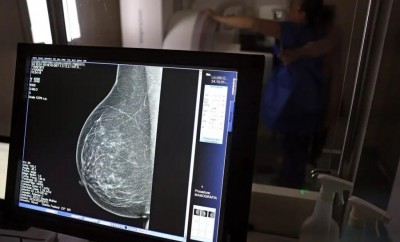

Em junho deste ano, 77.243 brasileiras aguardavam por uma mamografia no Sistema Único de Saúde (SUS). Santa Catarina é o estado com mais mulheres na fila de espera, cerca de 17 mil. Em seguida, aparecem São Paulo (15 mil) e Rio de Janeiro (12,5 mil). Juntos, os três estados somam 56% do total de pacientes à espera do principal exame para detecção do câncer de mama. Os dados foram divulgados nesta quinta-feira (31) pelo Colégio Brasileiro de Radiologia e Diagnóstico por Imagem (CBR).

Segundo a entidade, em alguns locais do país, o tempo de espera por uma mamografia na rede pública pode chegar a 80 dias. O exame, quando realizado em tempo hábil, permite a detecção precoce de alterações mamárias, aumentando as chances de tratamento bem-sucedido e reduzindo a necessidade de intervenções invasivas e onerosas. “Os números revelam parte da sobrecarga no SUS e devem ser levados em conta, especialmente pelos recém-eleitos nas eleições municipais, na formulação e manutenção de políticas de saúde pública”, avaliou o CBR.